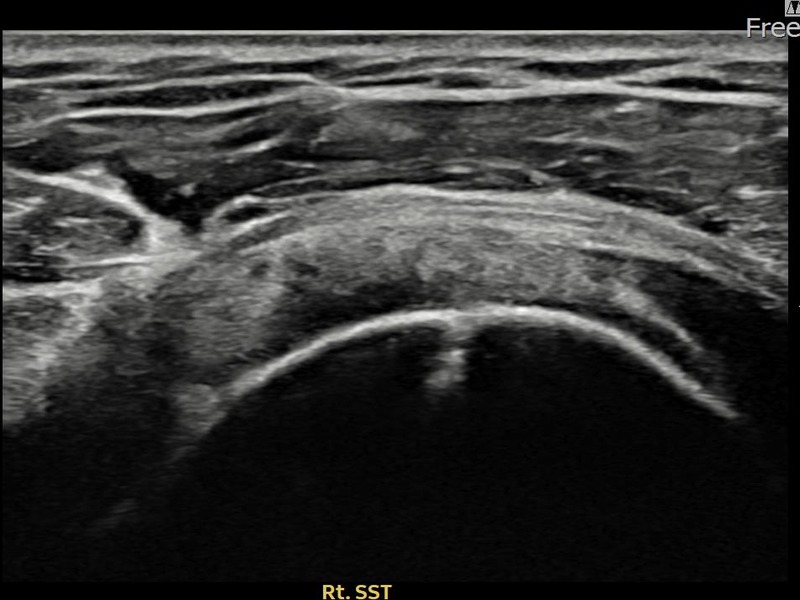

최ㅇㅇ님 · 우측 극상근건 관절면측 파열 진행형

우측 어깨 파열이 진행된 상태로 수술 없이 치료를 원해 내원하셨습니다. 다각도 초음파 평가 후 축소봉합술을 시행하여 힘줄 구조가 안정화되었습니다.

상세 보기 →